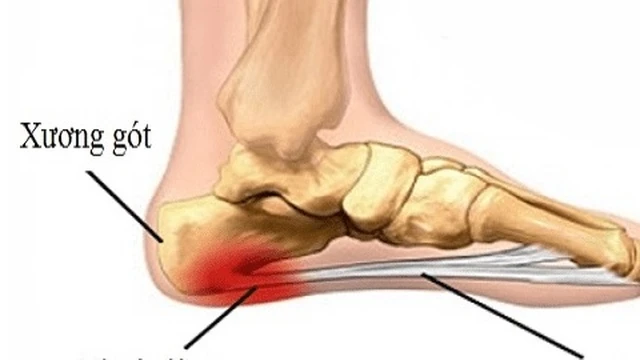

Gai xương gót là tình trạng đau nhức ở gót chân, khiến cho bạn khởi động ngày mới với sự đau đớn, khó chịu. Vậy đâu là nguyên nhân gây ra bệnh gai xương gót? Triệu chứng gai xương gót là gì và cách điều trị như thế nào? Hãy cùng Long Châu theo dõi bài viết dưới đây nhé.

Sáng ngủ dậy bị đau lòng bàn chân có thể do nhiều nguyên nhân gây ra. Có người do bị viêm cân gan bàn chân, cũng có trường hợp khác là do viêm khớp, tổn thương mô mềm do chấn thương hoặc gai xương. Dù là nguyên nhân gì thì cũng đều cần điều trị sớm để tránh viêm tiến triển.